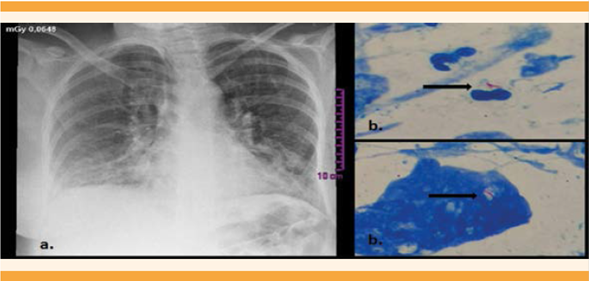

Paciente de 30 años, con antecedente de asma leve intermitente en tratamiento con salbutamol, dos embarazos, un parto y un aborto y una gestación en curso de 35 semanas atendida en el Hospital Universitario de la Samaritana, un centro de alto nivel de complejidad de Bogotá, Colombia. Acudió a consulta debido a un cuadro de 15 días de evolución consistente en picos febriles de 38 oC y tos, con siete controles prenatales sin complicaciones. Los signos vitales a su ingreso: tensión arterial de 128-91 mmHg, frecuencia cardiaca de 71 lpm, frecuencia respiratoria de 16 rpm, saturación de oxígeno de 92% al ambiente. En la auscultación pulmonar se detectaron estertores y sibilancias espiratorias en el hemitórax izquierdo, útero grávido con altura de 27 centímetros, feto único con 145 lpm; con impresión diagnóstica de crisis asmática leve y neumonía basal izquierda. Se hospitalizó para la realización de estudios complementarios. El hemograma se reportó sin leucocitosis, con diferencial leucocitario normal. La función hepática normal, lo mismo que la renal. La radiografía de tórax mostró radiopacidades de ocupación alveolar basales, bilaterales (Figura 1) y baciloscopia de esputo con bacilos alcohol resistentes: 9 bacilos por campo (Figura 1). Se estableció el diagnóstico de tuberculosis pulmonar, con neumonía bacteriana multilobar. El tratamiento indicado fue: ampicilina-sulbactam, isoniazida, rifampicina, etambutol, pirazinamida, piridoxina, nebulizaciones con beta 2 agonista y terapia respiratoria. Durante la hospitalización tuvo actividad uterina regular, con finalización del embarazo por parto, con un recién nacido de 2760 g, con adaptación neonatal espontánea y APGAR de 8-9-10 y examen físico normal. No se permitió el contacto con la madre y se hospitalizó en la unidad de cuidados intermedios por el riesgo infeccioso. El hemograma se reportó sin leucocitosis, con diferencial normal, proteína C reactiva negativa, radiografía de tórax normal, ecografía de abdomen total normal, prueba de derivado proteico purificado (PPD) negativa. Se inició el tratamiento profiláctico con 30 mg al día de isoniazida y 5 mg al día de piridoxina. En el trascurso de la hospitalización se obtuvieron los reportes de hemocultivos negativos, tres baciloscopias en jugo gástrico negativas y dos pruebas positivas PCR que detecta ADN de Mycobacterium tuberculosis en el jugo gástrico (Figura 2). Ante el hallazgo de la PCR se diagnosticó tuberculosis congénita y se incluyó al tratamiento del recién nacido: 30 mg al día de rifampicina y 40 mg al día de pirazinamida.

Figura 1 a) Radiografía de tórax de la madre con radiopacidades de ocupación alveolar basales y bilaterales. b) Baciloscopia del esputo de la madre (100 x) con bacilos ácido alcohol resistente, flechas.